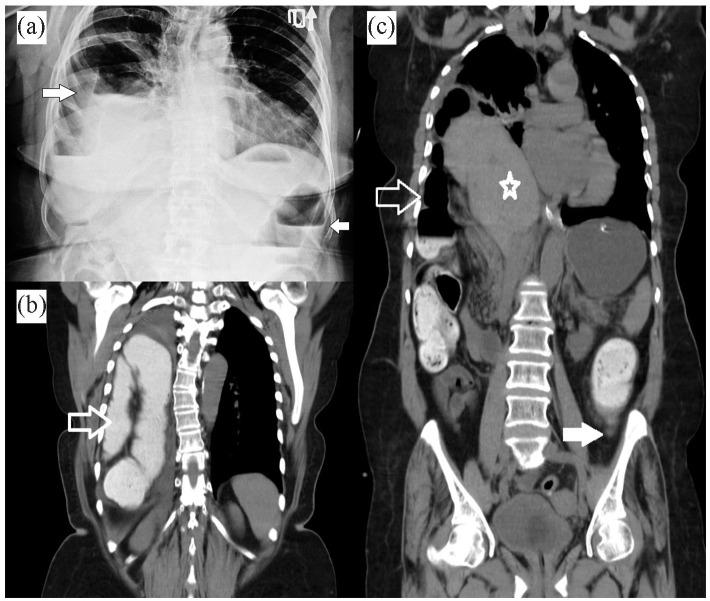

The adult Bochdalek hernia is one of the right-sided diaphragmatic hernias that less than 30 cases reported until now. Here, we report a 64-year-old female patient who presented with dyspnea, abdominal pain, and nausea. Primary imaging showed a right-sided diaphragmatic hernia that contained the liver and right colon. At first, the patient underwent a right posterior thoracotomy, and the diaphragmatic defect was repaired. After 2 days, abdominal peritonitis happened then a midline laparotomy was performed. Finally, it was clear that the main problem was the obstructed and perforated descending colon mass that was presented with Bockdalek hernia. Unfortunately, the patient passed away 2 days after the operation. It should be considered that an increase in intra-abdominal pressure like the presence of obstructed colon mass can cause this rare hernia and It is important to determine the reason for the presentation of the symptomatic Bochdalek hernia in adult patients.

成人博赫达勒克疝是右侧膈疝之一,迄今为止报道的病例不足30例。在此,我们报告一名64岁女性患者,她出现呼吸困难、腹痛和恶心症状。初步影像学检查显示右侧膈疝,疝内容物为肝脏和右结肠。起初,患者接受了右后外侧开胸手术,修复了膈肌缺损。术后2天,发生了腹部腹膜炎,随后进行了正中剖腹手术。最终明确主要问题是伴有博赫达勒克疝出现的降结肠肿块梗阻并穿孔。不幸的是,患者术后2天死亡。应考虑到像结肠肿块梗阻这样的腹内压升高可导致这种罕见疝,确定成人患者出现有症状的博赫达勒克疝的原因很重要。